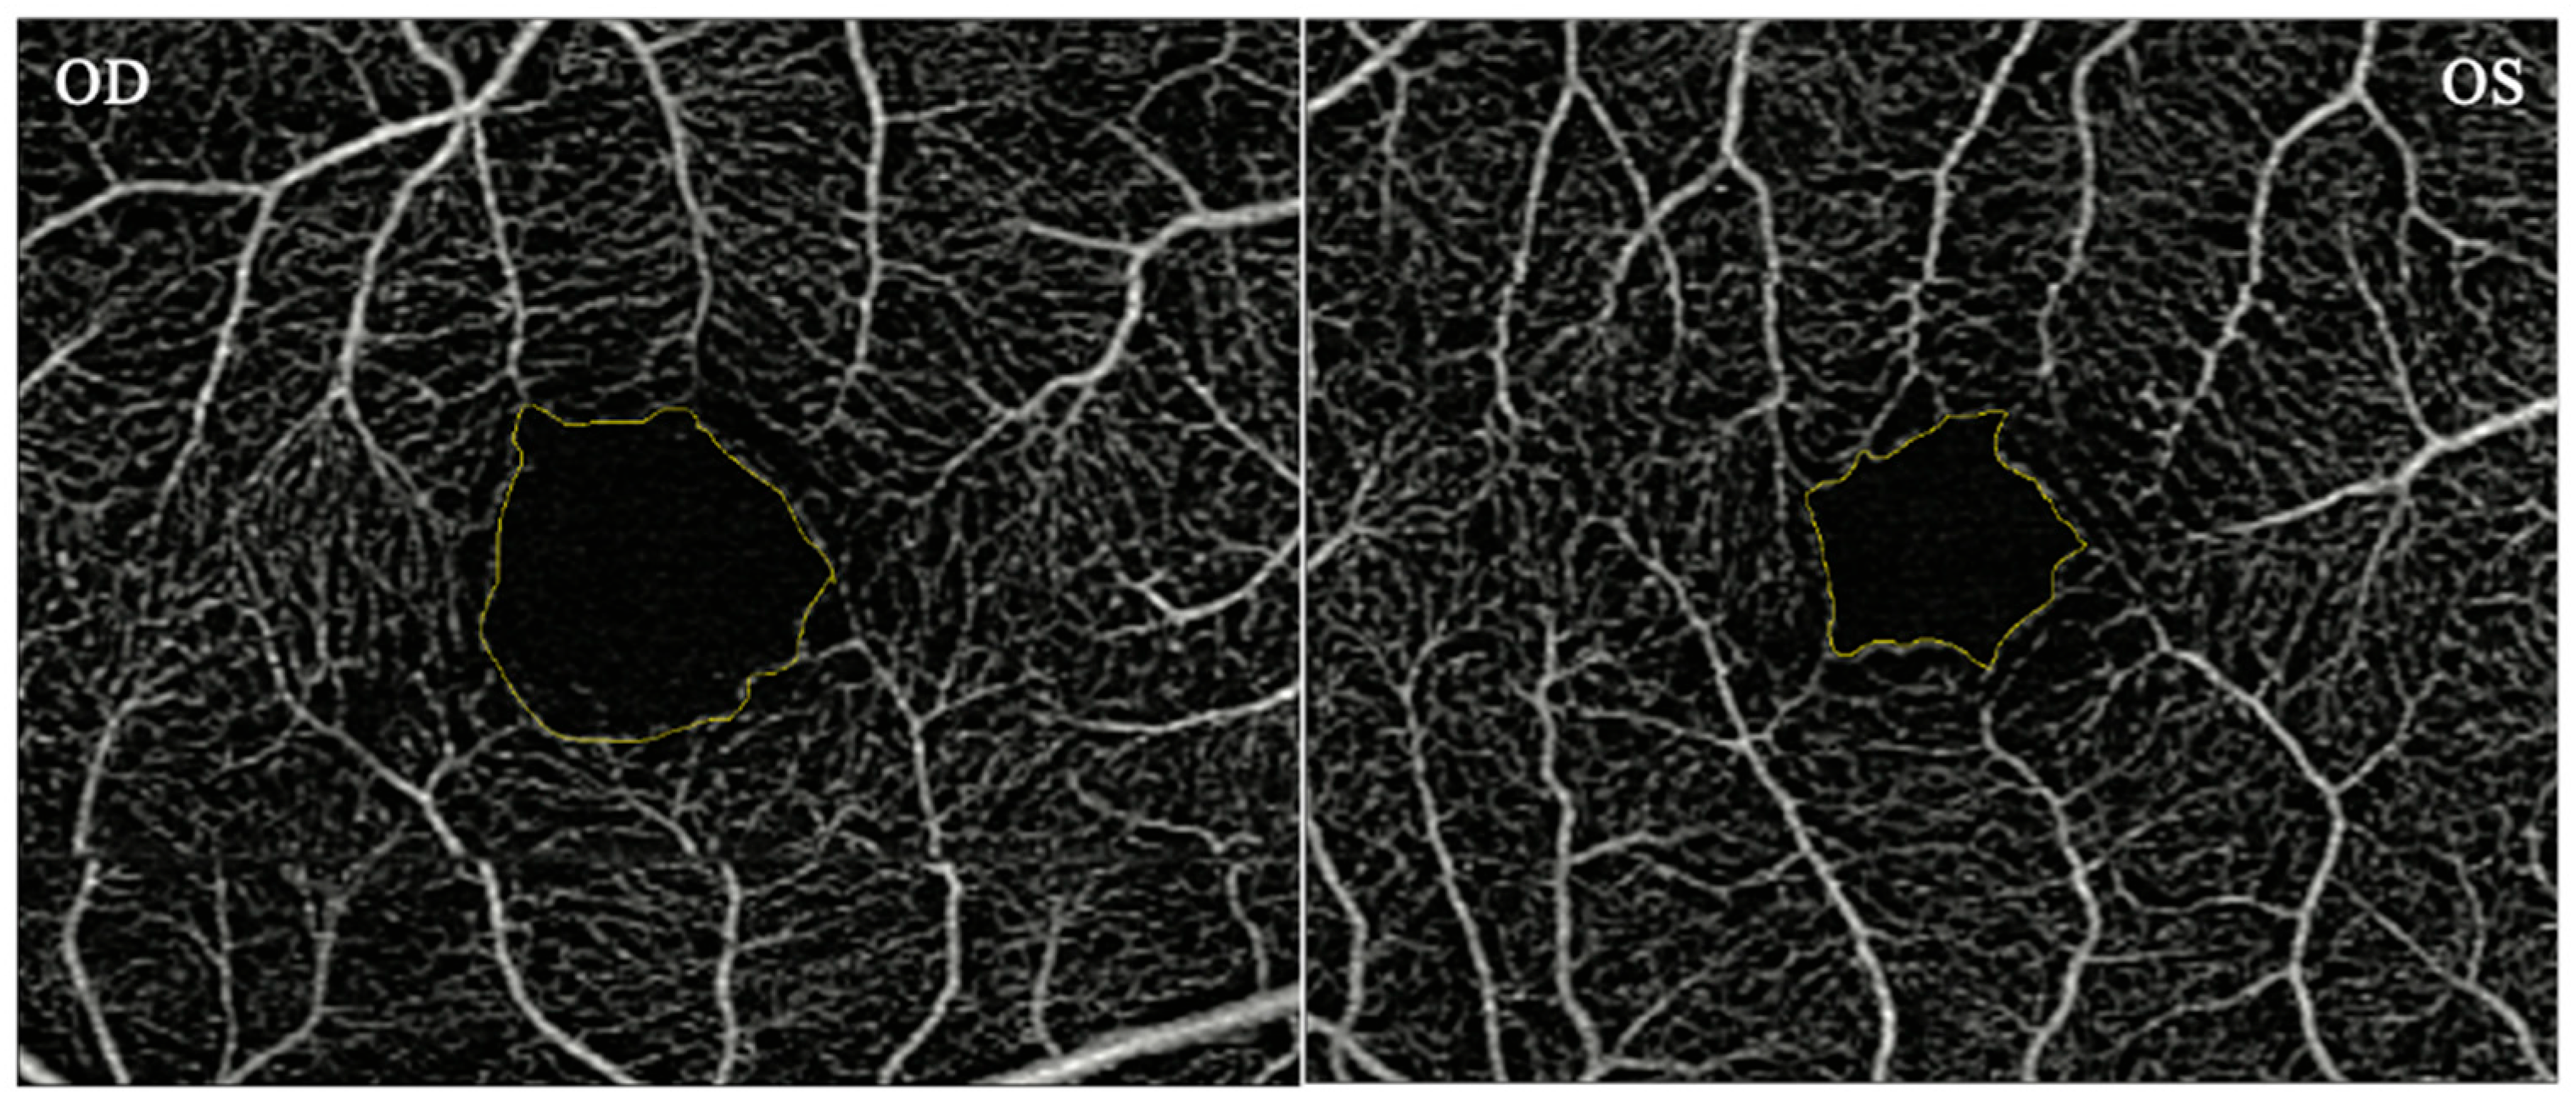

2.4.4. OCT Angiography (OCTA)

OCTA measurements of the macula for each eye were obtained using a Zeiss Cirrus HD-OCT 5000 with AngioPlex device (Carl Zeiss Meditec, Inc., Dublin, CA, USA). OCTA provides angiographs from the superficial, intermediate, and deep vascular complex. Scans measuring 3 × 3 mm (superficial retinal complex) were used in the study. The superficial vascular complex was used to obtain the macular FAZ area. The FAZ area was measured manually using ImageJ software. The intraclass correlation coefficient was 0.99 indicating a high degree of reliability between 2 raters (AT, JT) (Figure 1).

Figure 1. Macular OCT-angiogram demonstrating an enlarged FAZ area (left image). Macular OCT-angiogram demonstrating a FAZ area within normal limits (right image).